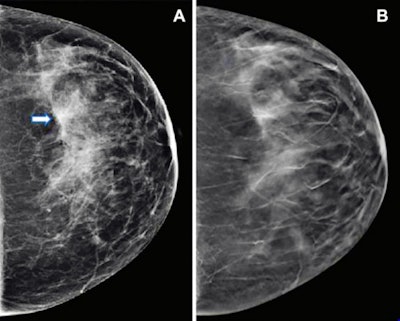

Images show mammography results in a 47-year-old woman who presented for routine screening. (A) Craniocaudal digital mammogram shows scattered fibroglandular densities. On the left digital mammographic craniocaudal view laterally, an asymmetry (arrow) is present. (B) Left craniocaudal DBT imaging shows no suspicious lesion, but rather a superimposition of normal fibroglandular and ligamentous structures. Images and caption courtesy of the RSNA.

Images show mammography results in a 47-year-old woman who presented for routine screening. (A) Craniocaudal digital mammogram shows scattered fibroglandular densities. On the left digital mammographic craniocaudal view laterally, an asymmetry (arrow) is present. (B) Left craniocaudal DBT imaging shows no suspicious lesion, but rather a superimposition of normal fibroglandular and ligamentous structures. Images and caption courtesy of the RSNA.They evaluated data from 2.5 million screening mammograms from 1.1 million women between the ages of 40 and 79. The women had no prior history of breast cancer and were screened from 2014 to 2020 in five U.S. healthcare systems. The researchers collected information from 1.7 million screening DBT exams and 834,336 screening mammograms from digital mammography.